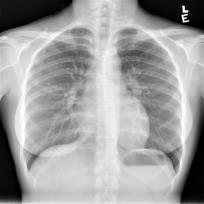

Chest X-ray (CXR) is the most typical radiological exam for diagnosis of various diseases. Due to the expensive and time-consuming annotations, detecting anomalies in CXRs in an unsupervised fashion is very promising. However, almost all of the existing methods consider anomaly detection as a One-Class Classification (OCC) problem. They model the distribution of only known normal images during training and identify the samples not conforming to normal profile as anomalies in the testing phase. A large number of unlabeled images containing anomalies are thus ignored in the training phase, although they are easy to obtain in clinical practice. In this paper, we propose a novel strategy, Dual-distribution Discrepancy for Anomaly Detection (DDAD), utilizing both known normal images and unlabeled images. The proposed method consists of two modules, denoted as A and B. During training, module A takes both known normal and unlabeled images as inputs, capturing anomalous features from unlabeled images in some way, while module B models the distribution of only known normal images. Subsequently, the inter-discrepancy between modules A and B, and intra-discrepancy inside module B are designed as anomaly scores to indicate anomalies. Experiments on three CXR datasets demonstrate that the proposed DDAD achieves consistent, significant gains and outperforms state-of-the-art methods. Code is available at https://github.com/caiyu6666/DDAD.

翻译:切斯特X射线(CXR)是诊断各种疾病的最典型的放射检查;由于昂贵和耗时的注释,发现CXR中异常现象非常有希望;然而,几乎所有现有方法都把异常检测视为单类分类(OCC)问题。它们模拟培训期间仅传播已知的正常图像,并将不符合正常特征的样本作为测试阶段的异常点,因此在培训阶段忽略了大量含有异常点的未贴标签图像,尽管这些图像在临床实践中很容易获得。在本文件中,我们提出了一个新颖战略,即使用已知的正常图像和未贴标签图像来检测非异常点检测(DDDD),使用已知的正常图像和未贴标签图像。拟议方法包括两个模块,即A类和B类。在培训期间,A单元将已知的正常和未贴标签图像作为投入,以某种方式从未贴标签图像中捕捉出异常点特征,而模块B类则只模拟已知的正常图像的分发。随后,A类和B类异点检测模块之间的不易位性(D级)和B类内部的变异性模型显示已设计为稳定的变数。